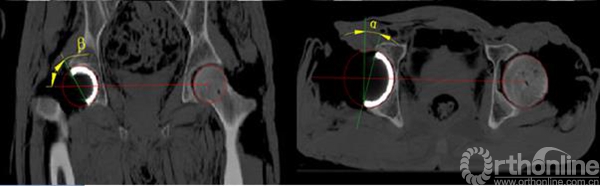

我们将对照侧髋臼表面点云的最适拟合球心坐标的镜像定义为HJC。通过3-matic6.1 软件建立水平位和冠状位的辅助平面,分别获得骨盆二维平面上的投影并测量得到髋关节的旋转中心O1和髋臼的方位(如图7)。再通过三角函数的关系计算得到髋臼旋转轴上的一个点(O2)(如图8)。连接O1O2两点的直线就代表了髋臼的旋转轴,也就是模板导航管的方向,沿计算好的髋臼旋转轴植入一虚拟髋臼杯假体,可以实现三维可视化观察,判断预期臼杯植入的效果(如图9)。

图7通过骨盆冠状面、水平面两个投影平面测得髋臼方位。

图8 图中O1为髋中心,利用三角函数的关系计算得到髋臼旋转轴上的O2。

图9 将虚拟髋臼杯沿髋臼旋转轴线植入到髋臼进行模拟观察。

利用逆向技术建立与髋臼卵圆窝表面解剖形状一致的反向模板,以髋臼旋转轴线为中轴线确定导航管的方向,设计出虚拟的髋臼卵圆窝导航模板,沿导航管植入一定位针代表髋臼旋转轴,判断手术植入的效果(如图10)。

研究表明,通过建立骨盆的辅助平面,结合三维信息的采集和二维平面的测量获得的髋臼外展角和髋臼前倾角更加接近其生理角度。以健侧为参照,根据对称性原理建立模板侧髋臼方位具有可靠的精确度,又避免了变异的解剖特点对测量结果的影响。